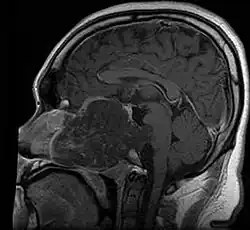

• Maximal resection followed by proton beam irradiation.

• Overall survival is dependent upon local control of disease. Prognostic factor for local control of disease is amount of residual tumor after original surgery (<25cc residual tumor is better).

• Clear margins are achieved in <50% of skull base chordomas.

• Doses of 70 CGE necessary for control of residual disease.

Skull Base